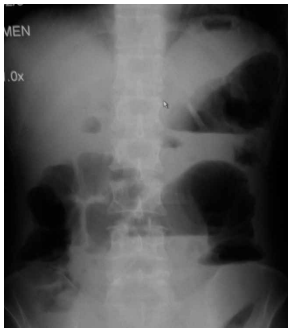

(Arquivo pessoal; imagem usada com autorização)